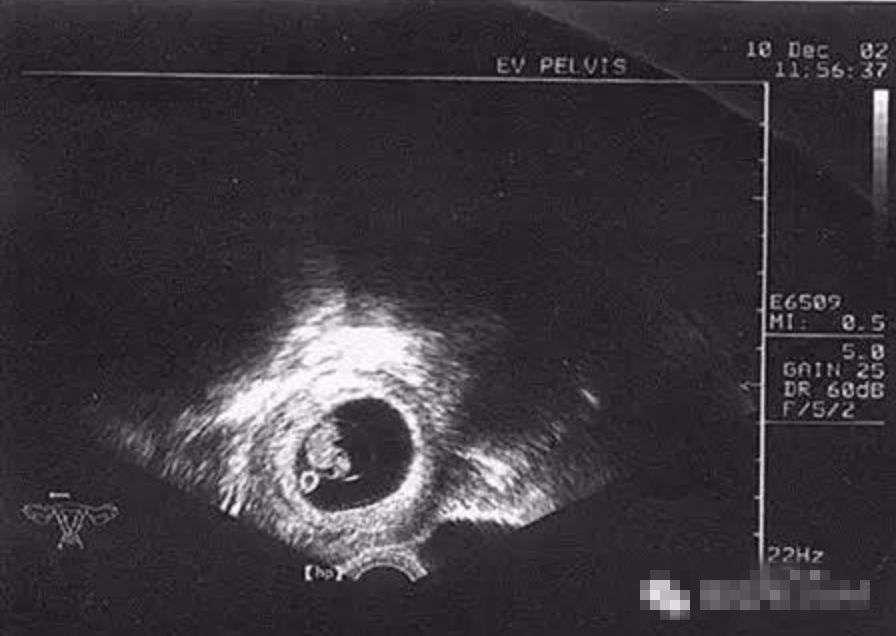

移植后14天复查HCG 1107.36mIU/mL,移植后33天超声提示:宫内早孕,已可见胎心搏动。